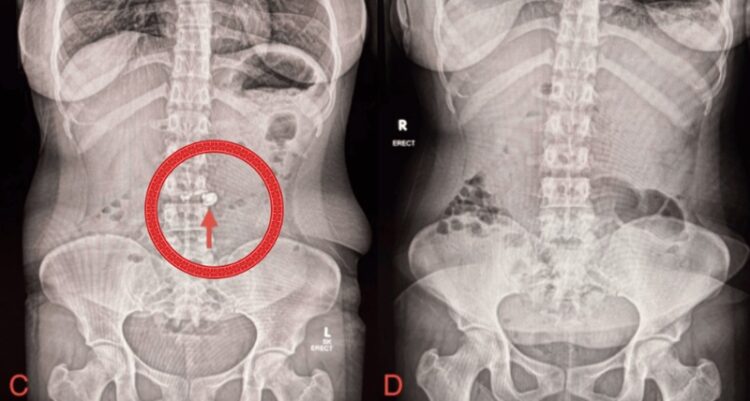

배터리가 포함된 전자기기를 삼키면 보통 이물질 위치를 파악하기 위해 복부 엑스레이 촬영을 한다. 스파르시병원 의료진도 엑스레이 촬영을 했고, 여성의 십이지장에서 이어폰으로 보이는 이물질이 관찰됐다.

의료진은 여성 몸속에서의 이물질 이동을 계속 지켜보던 중, 이물질 섭취 후 5일째에 시행한 복부 엑스레이 촬영에서 이물질이 보이지 않는 것을 확인했다. 의료진은 이어폰이 자연적으로 배출된 것으로 판단했다.